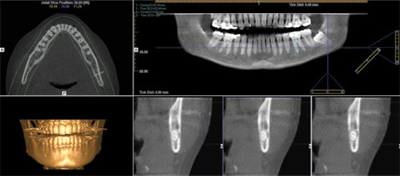

I-CAT Vision

I-CAT Vision é um software que gera imagens, onde integram módulos de visualização para ATM, implante e todos os cortes axiais, coronais e sagitais.